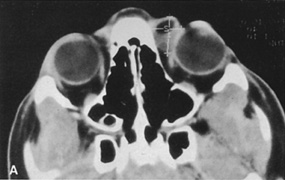

Figure 10. A. Large, well-encapsulated intraconal mass on MR scan. B. Small lateral canthotomy incision will be used to perform lateral orbitotomy and remove the intraconal mass.

Fig. 11. A. Lateral canthotomy incision is made with straight iris scissors. B. Periosteum is elevated off of the lateral orbital rim. C. Wide undermining allows retraction of the skin incision to permit superior and inferior osteotomies to be made with the air-driven saw. D. The bony rim has been outfractured. Because of the distensibility of the skin, it is possible to remove a large bone flap through the small canthotomy incision. E. The intraconal mass is extracted with the aid of the cryoprobe. F. The bone fragment is positioned for resuturing.

Fig. 12. A. The lateral canthotomy incision is reapproximated with simple closure of the superior and inferior crura of the lateral canthal tendon. A drain from the temporal fossa has been brought out through a separate stab incision posteriorly. 12B. Excellent postoperative scar camouflage is obtained by this approach.